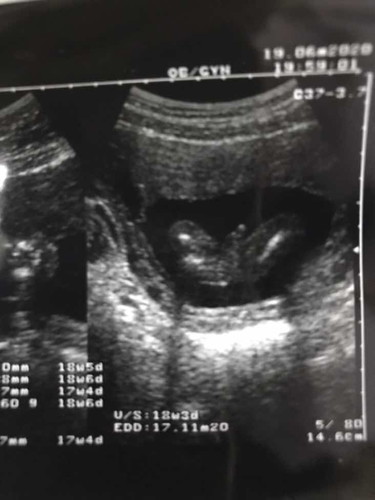

4 เดือน 2 สัปดาห์ 4 วันชัดเจนมากลูกหนูโชว์ให้แม่เห็นขนาดนี้คงไม่มีโอกาสที่จะออกมาเป็นผญ.แน่นนอนสมใจคุณพ่อเขาแหละ จะผญ.หรือผช.ก้รักหมดลูกชายหัวแก้วหัวแหวนของพ่อแม่ ☺️💓👶🏻